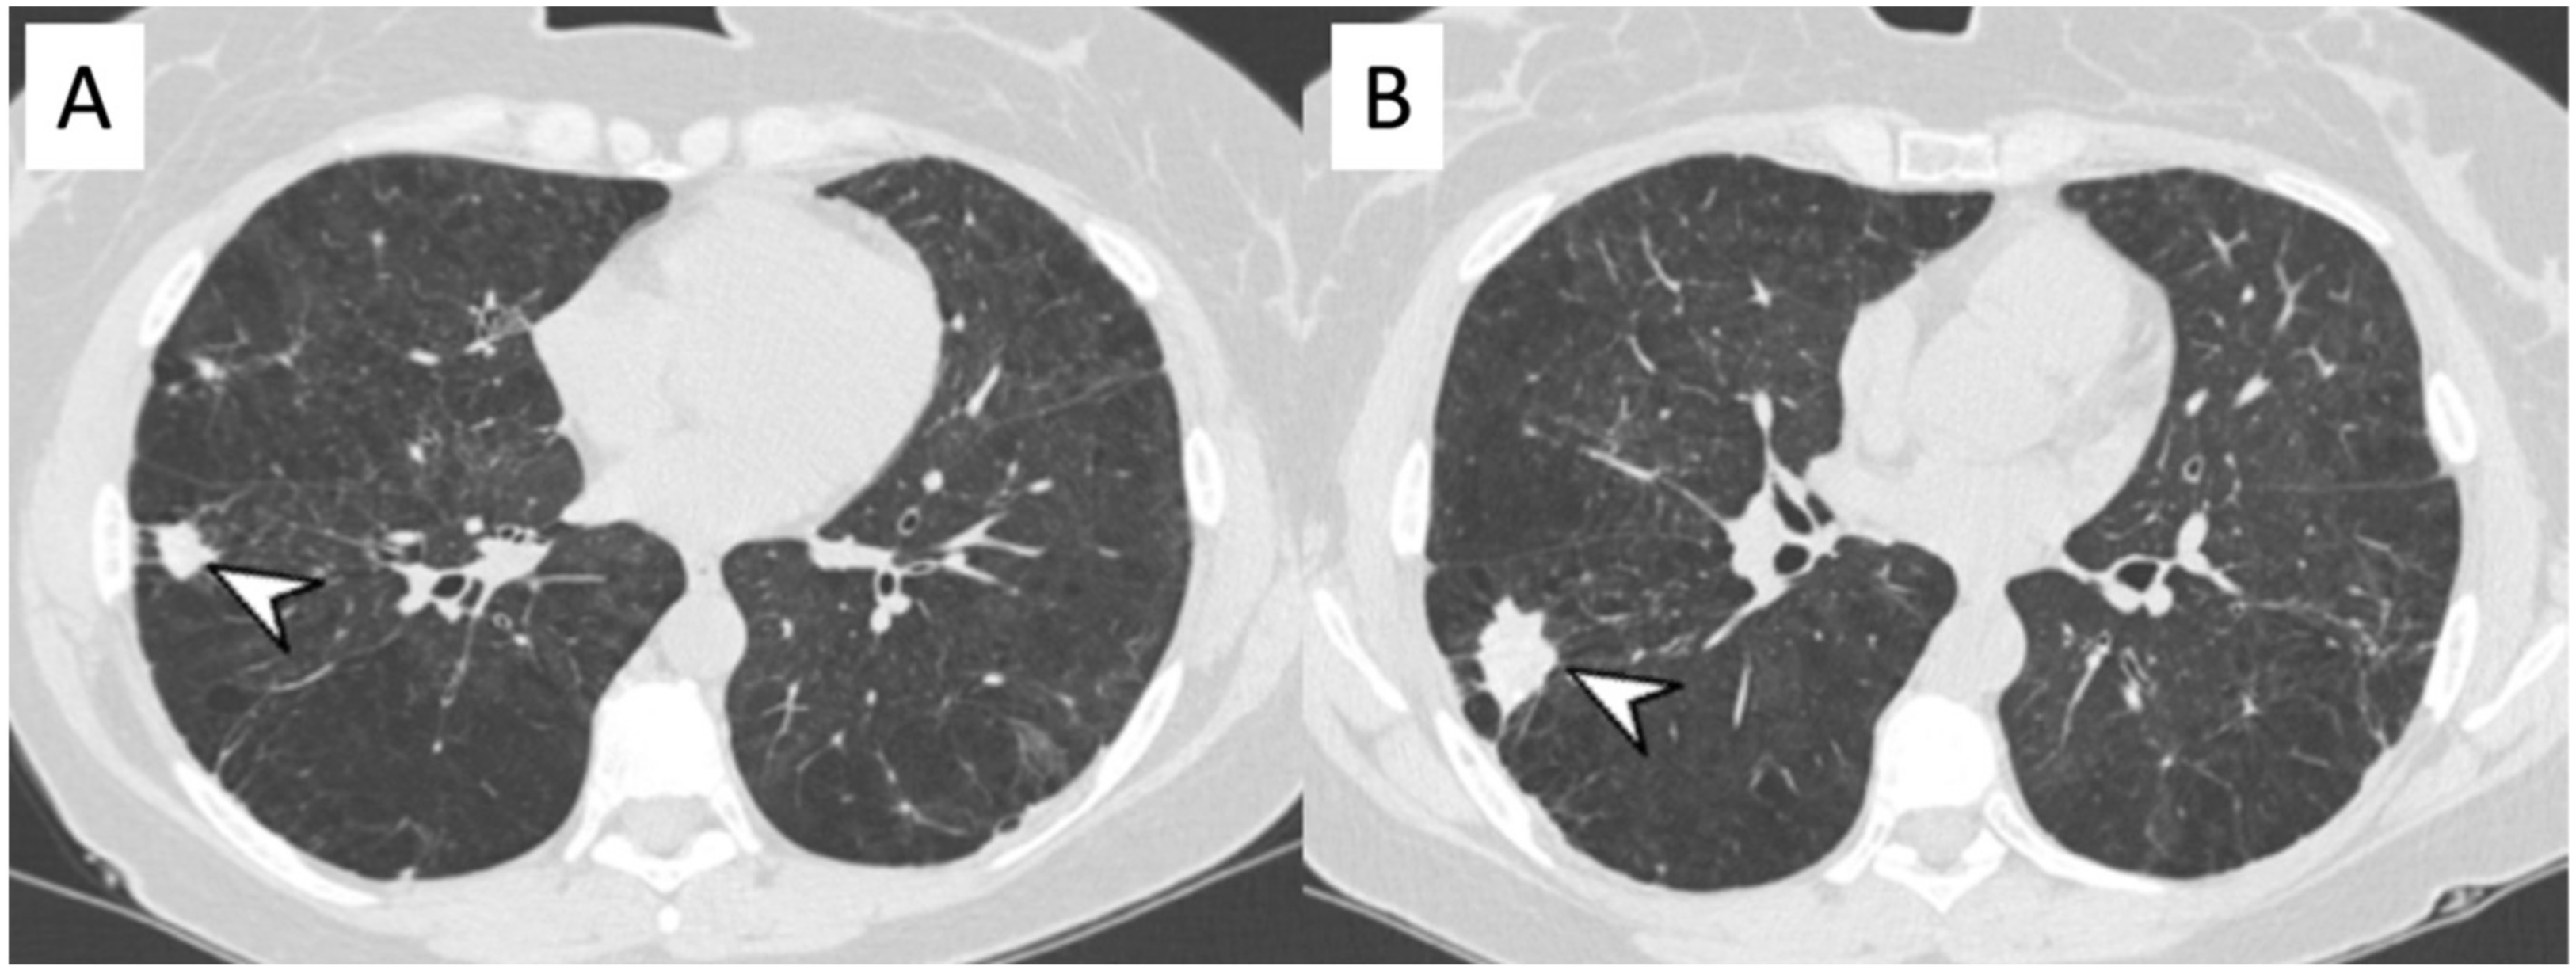

2.3. Microscopic Polyangiitis (MPA)

2.10. ILD in ANCA-Associated Vasculitides

2.10.2. Morphological Patterns and Imaging